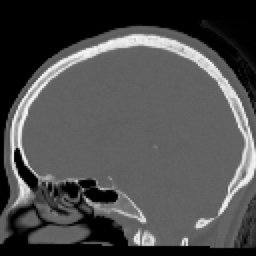

- RESUMEN TOMOGRAFIA

SIMPLE FINO (4) 129 images

HUESO FINO (5) 129 images

ARTERIAL FINO (7) 129 images

SIMPLE FINO COR (8) 91 images

SIMPLE FINO SAG (9) 75 images

ARTERIAL FINO COR (10) 90 images

ARTERIAL FINO SAG (11) 78 images

HUESO FINO COR (13) 90 images

HUESO FINO SAG (14) 75 images

HUESO FINO 3D (Creator:CT1) (100) 72 images